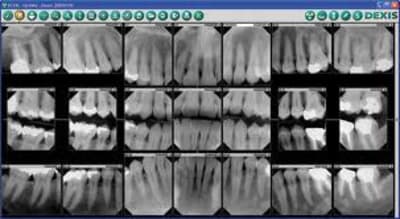

Le meilleur copain (dentiste) de mon beau-père étant parti à la retraite, mon beau-père est venu me voir au cabinet car "quelque chose est tombé de sa prémolaire".

J'ai fait une couronne sur dent vivante sur la 25.(j'ai après avoir pris la radio supprimé l'excédent de ciment)

Mes questions: les amalgammes sur les 16,15,26,36 et 37 étant très volumineux, est-il possible de faire des onlays ?

Si non, couronnes sur dents vivantes ? sur quelles substances restantes vu ce qu'il restera après avoir déposer les amalgammes ?

Il n'y en a plus beaucoup de vivantes : commence d'abord à refaire les traitements canalaires si tu veux entreprendre quelque chose/ A ta place,j'attendrais d'avoir un peu plus d'expérience car il s'agit d'une réhabilitation plus ou moins complète. C'est sûr que son meilleur copain avait moins de scrupules, ou tout simplement de compétences.

Tu peux envisager des onlays, parce que vu le volume des amalgames je ne vois pas comment faire de couronne sans dévitaliser.

Pas d'accord avec les reprises d'endo systématiques.

Je ne vois pas de granulomes.

Les joints ont l'air bien étanches, la morphologie occlusale est parfaite, tout comme les points de contact d'ailleurs.

Couronner ou onlayter sur des endos comme celles-ci... C'est quand même un peu du foutage de gueule, non?

Systématiques non, mais systématiques pour ce patient, oui...

Il n'y a pas une endo correcte.

Ne pas reprendre pour épargner une petite douleur immédiate supposée, et faire risquer au patient des infections péri-apicales quasi certaines dans quelques années, c'est...paradoxal ^^

En tout 1er, tx paro, il y a du tartre partout, non mais...

Bon, photo de qualité, bilan radio plus complet et analyse d'occlusion.

primum non nocere... Les endo ne sont pas terribles, c'est le moins qu'on puisse dire, MAIS: de quand datent-elles? Il ne semble pas y avoir d'images apicales, le patient est plutôt âgé, est-il utile de tout refaire excepté l'amalgame de la 16(?) qui est défectueux, est-il vraiment demandeur?